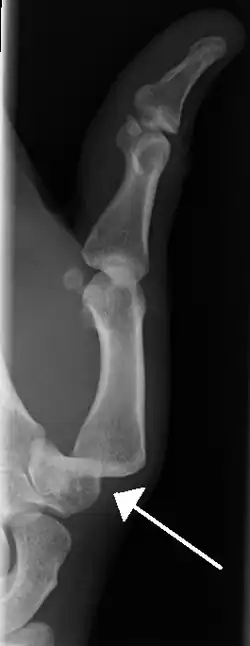

Prognosis varies depending on the location and extent of the dislocation. The prognosis of a shoulder dislocation is dependent on various factors including age, strength, connective tissue health and severity of the injury causing the dislocation.[23] There is a good prognosis in simple elbow dislocations in younger people. Older people report more pain and stiffness on average.[23] Wrist dislocations are often difficult to manage due to the difficulty in healing the small bones in the wrist.[23] Finger displacement towards the back of the hand is often irreducible due to associated injuries, while finger displacement towards the palm of the hand is more readily reducible.[23] Overall, recovering from a joint dislocation can range from a few weeks to months, depending on the severity of the injury.[4]

• Finger

• Interphalangeal (IP) or metacarpophalangeal (MCP) joint dislocations[41]

• In the United States, men are most likely to sustain a finger dislocation with an incidence rate of 17.8 per 100,000 person-years.[42] Women have an incidence rate of 4.65 per 100,000 person-years.[42] The average age group that sustain a finger dislocation are between 15 and 19 years old.[42]

• The most common dislocations are in the proximal interphalangeal (PIP) joints.[8]